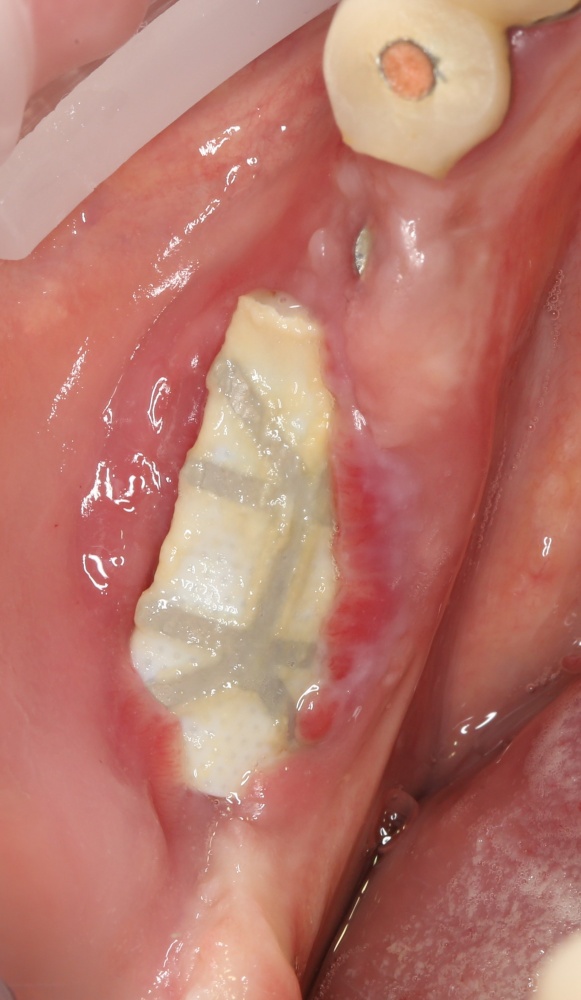

Итак, Зинаида на приеме.

Вот клиническая картина через 4 месяца после ранее проведенной имплантации с остеопластикой:

Как видишь, коллеги из недалекой дружественной страны не осилили снятие швов. Мне это не нравится, хотя и объясняет, почему люди готовы ехать за тыщи километров ради 20-минутной операции удаления зуба мудрости.

Ну хорошо. Швы сняли. Делаем разрез. Обрати внимание, что после всех проведенных операций у нас остается очень небольшой по ширине слой жевательной слизистой оболочки: